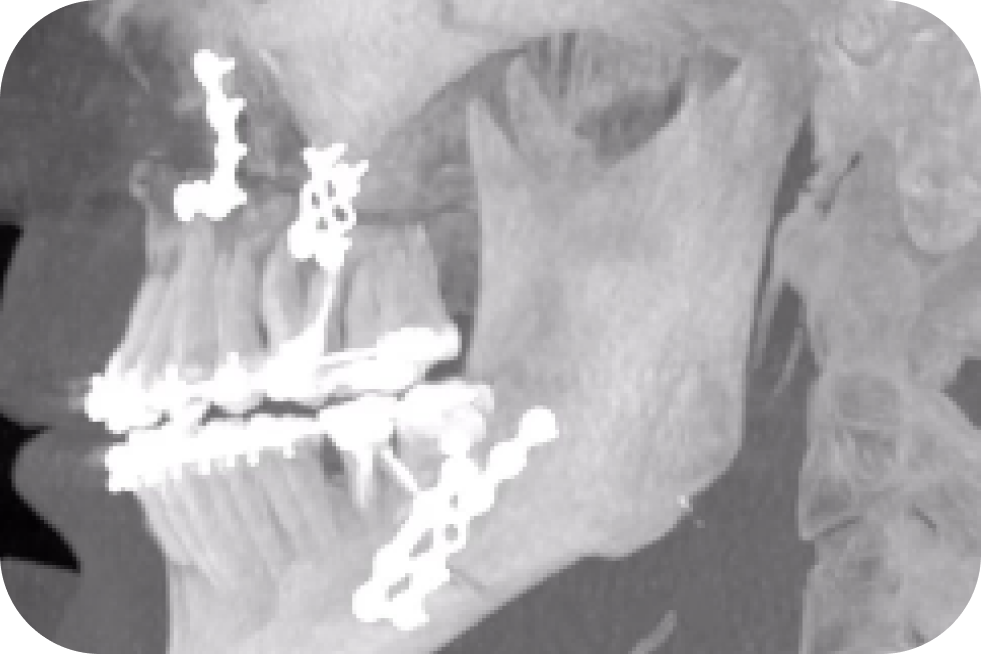

Нужно ли снимать минипластины?

Минипластины можно оставить и не снимать.

Если они «дают о себе знать»: возникает воспаление или расшатываются винты, появляются свищи — то их непременно удаляют.

Также удаление возможно по желанию пациента. Некоторые хотят снять их принципиально, так как им не нравится что в их теле находится «инородное тело».

Операцию проводят минимум через 9 месяцев на нижней челюсти и 12 месяцев на верхней челюсти.